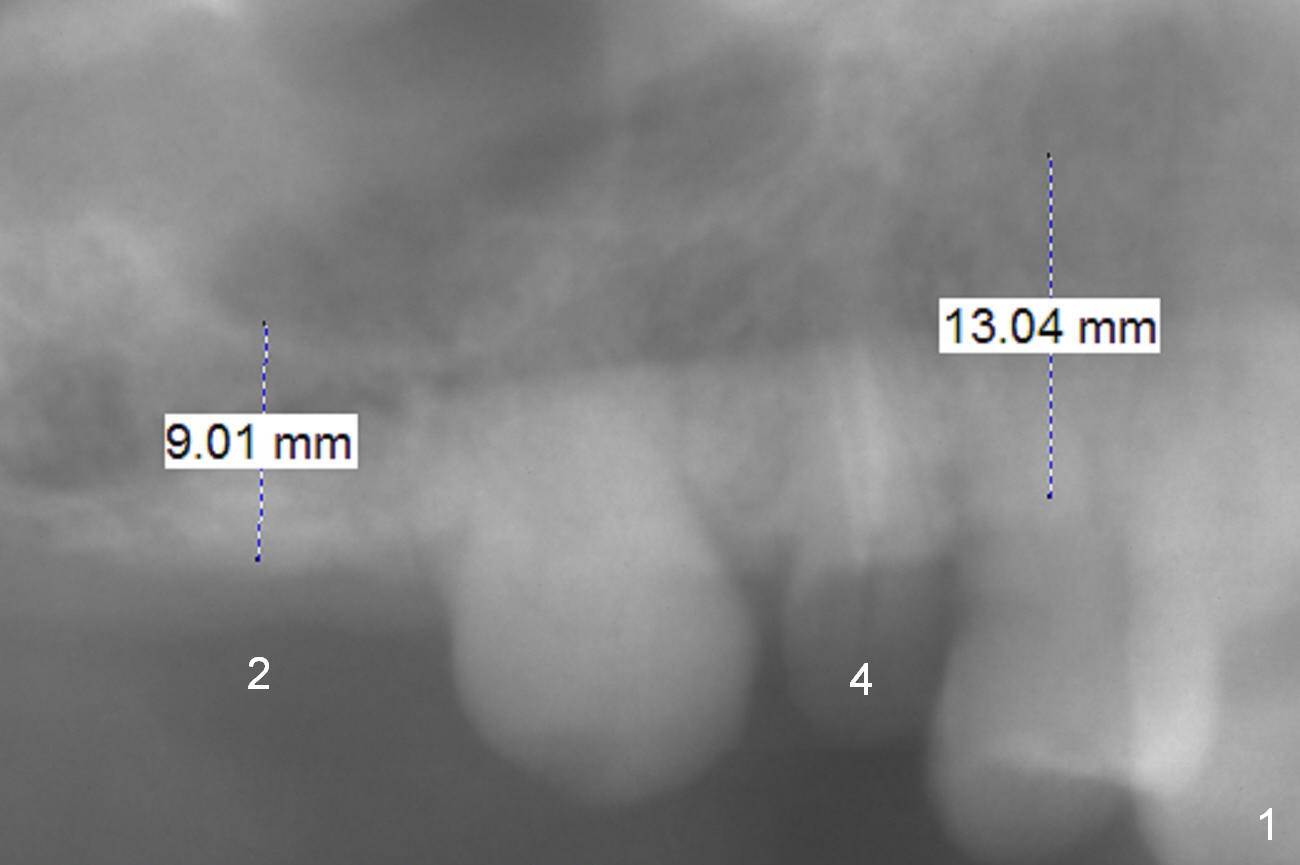

A 73-year-old man (HR) requests restoration at #2-4 (#3 lost crown). To prevent buccal plate fracture associated with extraction at #4, the buccal portion of the root will be preserved (socket shield, surgical bur block) after buccal sulcus incision. Still prepare proximators for extraction. Granulation tissue is going to be removed, followed by Clindamycin. Since there are two canals, start osteotomy using Magic Expander (ME) 3 mm in the palatal portion of the socket apex (oval) for 2 mm. Insert a 4 or 4.5x11 mm dummy implant and take PA to determine placement level. Osteotomy at #2 will begin with Magic split, followed by ME for 9 mm. Use drills if bone density is high. Sinus lift will be done at the sites. An immediate splinted provisional will be fabricated by hand at #2-4.

Return to Upper Premolar Immediate Implant, IBS, Magicore Cases Xin Wei, DDS, PhD, MS 1st edition 11/11/2016, last revision 09/16/2018